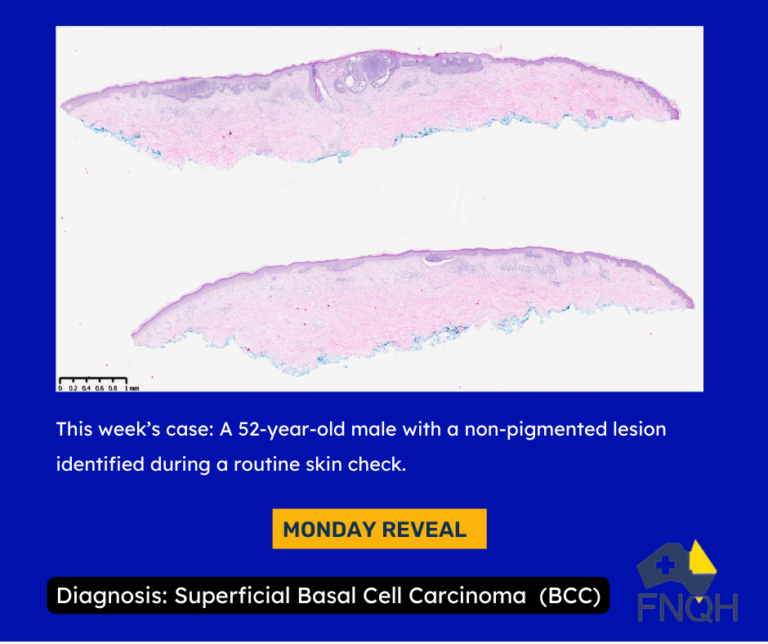

Week One

We post a new case with the clinical image and brief details.

Week Two

We reveal the diagnosis and microscopic findings.